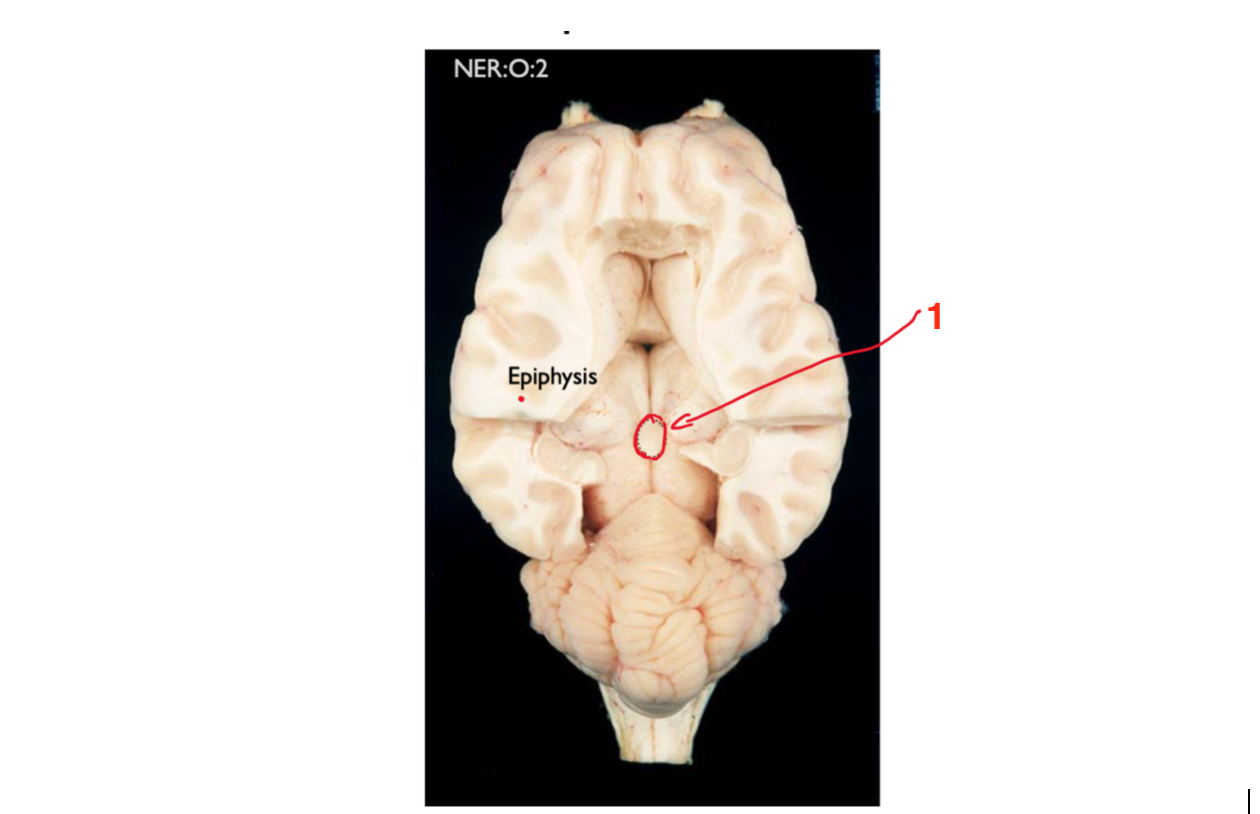

Name the structure circled and state it’s function:

Epithalamus (pineal gland) - the main function of it is that it secretes melatonin